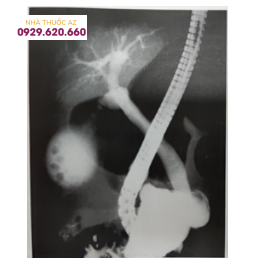

Tư thế này về mặt lý thuyết cho phép tiến hành dễ hơn khi đầu ống soi qua môn vị vào tá tràng. Sau khi vào được tá tràng thì lăn bệnh nhân vào tư thế nằm sấp nhiều hơn. Thủ thuật này đòi hỏi phải có sự trợ giúp của kỹ thuật viên vì lúc này bệnh nhân đã được dùng tiền mê giảm đau hoặc gây mê nội khí quản.Tư thế này có thể dễ dàng cho việc đưa ống nội soi vào tá tràng.Hiện nay, khi bệnh nhân lên bàn nội soi hay bàn X quang, một tư thế đặc biệt nằm nghiêng trái (T) hơi sấp. Mông phải (P) cao hơn, chân (P) co lên để xác định xem barium đó đã được bài tiết hết chưa. Nếu barium vẫn còn đọc được trên phim quang tuyến, thì việc chỉ định dùng thuốc xổ phù hợp vào buổi chiều hôm trước sẽ đảm bảo vùng mật-tụy mà nội soi cần khảo sát không còn chồng hình, nếu không sẽ bỏ sót thương tổn ở đường mật-tụy chỉ vì lý do này

Barium còn đọng ở khung đại tràng che lấp một phần hình ảnh ống mật chủ vùng nhú Vater